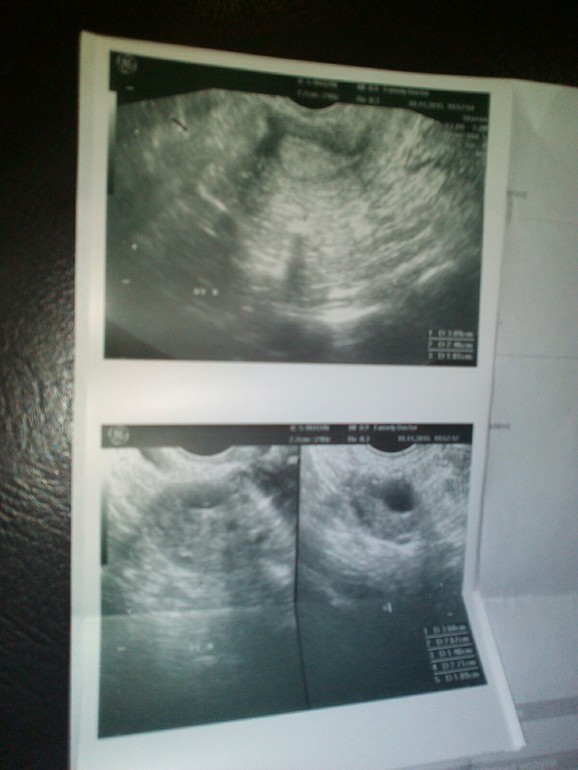

Узи....пусто

Овуляция( тесты на овуляцию)Девочки все пусто, врач сказал что все опухло,как перед месячными..жт есть, даж намека на Б нет!!!!!! Ждите месячных...завтра после завтра...

В смысле пусто? Вы думали там уже эмбриона увидеть? Рано ещё, не раньше 7 недель беременности.

Конечно,нет! Вы вообще, можете представить,насколько плодное яйцо крошечное на таком сроке? Просто невероятных размеров.Не придумали ещё такой чудо техники,что бы на раннем,при раннем даже,сроке увидеть эту точечку. Ну,вы сами-то подумайте!

Ну так рано вы пошли то.плод виден не ранье чем через неделю задержки

Я так понимаю, что тесты положительные, ЖТ есть, больше ничего и не увидели бы в 1 дз. Сдайте хгч, если М не придут

Б и не увидели б в 1 дз. А тесты не делали? То, что ЖТ ещё есть (оно перед М исчезает) хороший знак) Может ещё есть шанс?)